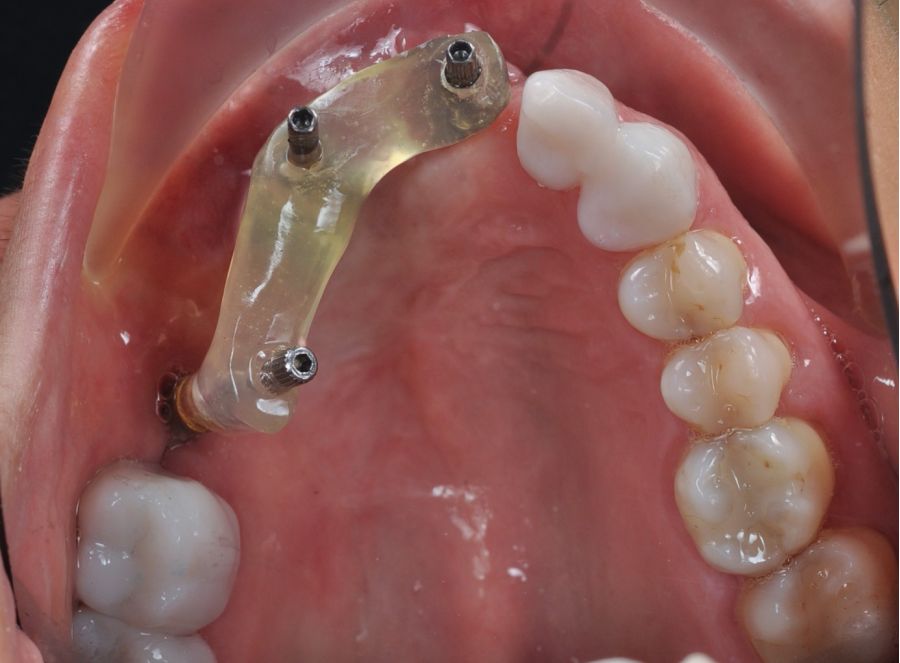

Bajo anestesia general, se realizó la resección quirúrgica junto con la fijación de dos placas preformadas y colocación simultánea de dos implantes cigomáticos y un implante endoóseo en posición del 2.1 (Figuras 5 y 6). Debido a la presencia de márgenes quirúrgicos comprometidos en el informe anatomopatológico, se indicó la administración de radioterapia adyuvante. Por este motivo, se decidió realizar un puente provisional dentosoportado de 1.7 a 2.3 (Figura 7) para mejorar la situación estética y funcional de la paciente durante todo el proceso y evitar un colapso de los tejidos blandos por la radioterapia. Para ello, se tallaron los molares (1.7, 1.6) e incisivo lateral y canino (2.2, 2.3), y se fabricó un puente fresado en polimetilmetacrilato (PMMA) con refuerzo metálico (Figuras 8 y 9).

Una vez finalizada la radioterapia, la paciente se encontraba libre de enfermedad. Por lo que se procedió a la restauración definitiva implantosoportada. Tras la segunda fase, se colocaron dos pilares transepiteliales Multiunit Ò rectos y un pilar Multunit Ò angulado de 17º (Figura 10).